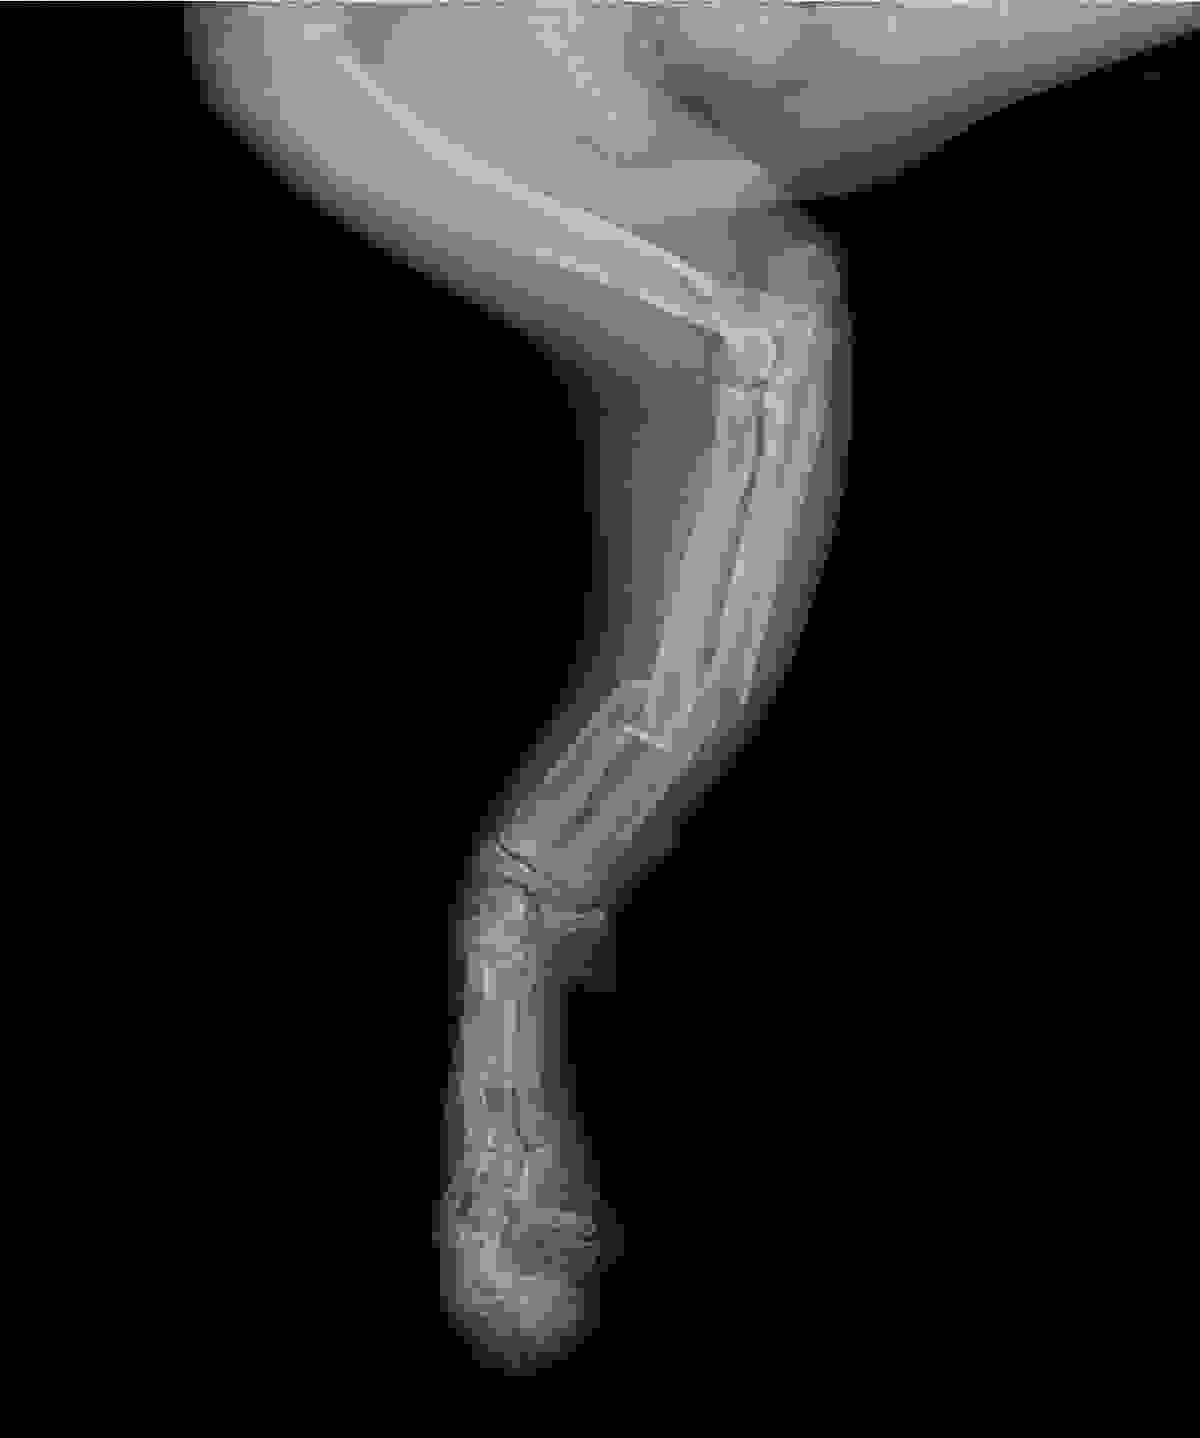

VEC的骨科服務建基於先進的醫療技術與緊密的團隊合作。中心採用國際認可的SecurosTM骨科用品,提供高品質的骨板、骨釘及外固定選項,以應對各類骨折修復與關節穩定手術。手術前,獸醫團隊會利用電腦斷層掃描獲取詳盡的立體影像,為制定精準的手術計劃提供關鍵資訊。

VEC每年處理過百次骨科及軟組織手術,常見病例包括小型犬的骨折修復及膝關節異位矯正。Dr. Hannah指出 :「在VEC,骨科病人會得到深切治療部及住院團隊的全面支援。手術前,他們能幫助危殆的動物穩定情況 ; 手術後,,提供密切的監測與護理,確保即使是最複雜的病例,在整個治療過程中都能得到最安全的管理。」

「我處理過其中一個難忘的病例,是一隻由高處墮下的貓咪(Tun Tun)送抵急症室時情況危殆,伴隨內出血及多處骨折。在ICU團隊的深切治療下,Tun Tun奇蹟般地穩定下來並成功接受了骨折修復手術。VEC跨團隊的無縫合作,是牠最終能康復成一隻活潑貓咪的關鍵。」Dr. Hannah分享道。與此同時,VEC亦有提供上門診症服務,讓寵物安在家中同時獲得醫療服務,跟進康復情況。